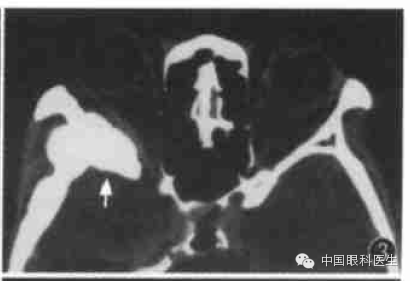

眶内静脉曲张常规CT扫描时多不显影,或仅显示小部分病变,欲观察病变全部范围可行颈部加压检查(图1,图2)。将血压计袋缠于患者颈部,摆好位置,加压至5.33kPa(高于静脉压),再行扫描检查,扫描完毕后立即将气囊放松。

图1左眶静脉曲张,平扫CT显示左眶后少许软组织密度(箭头)

图2同例静脉曲张加压后CT显示左眼球明显出土,球后出现巨大高密度软组织块影(箭头)